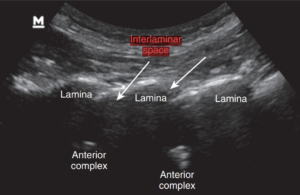

نخاع در تمام طول ستون فقرات، در داخل مهرهها و توسط سه لایه محافظ احاطه شده است.

خارجیترین لایه، دورا (Dura) نام دارد.

به فضای بین این لایه و سطح داخلی مهرههای ستون فقرات، فضای اپیدورال گفته میشود که با بافت چربی و عروق کوچک پر شده است.

در تصاویر زیر، این فضا با هایلایت سبز مشخص شده است.